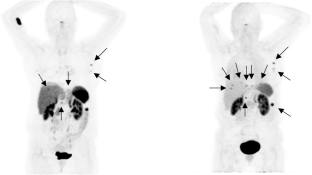

Fig. 1